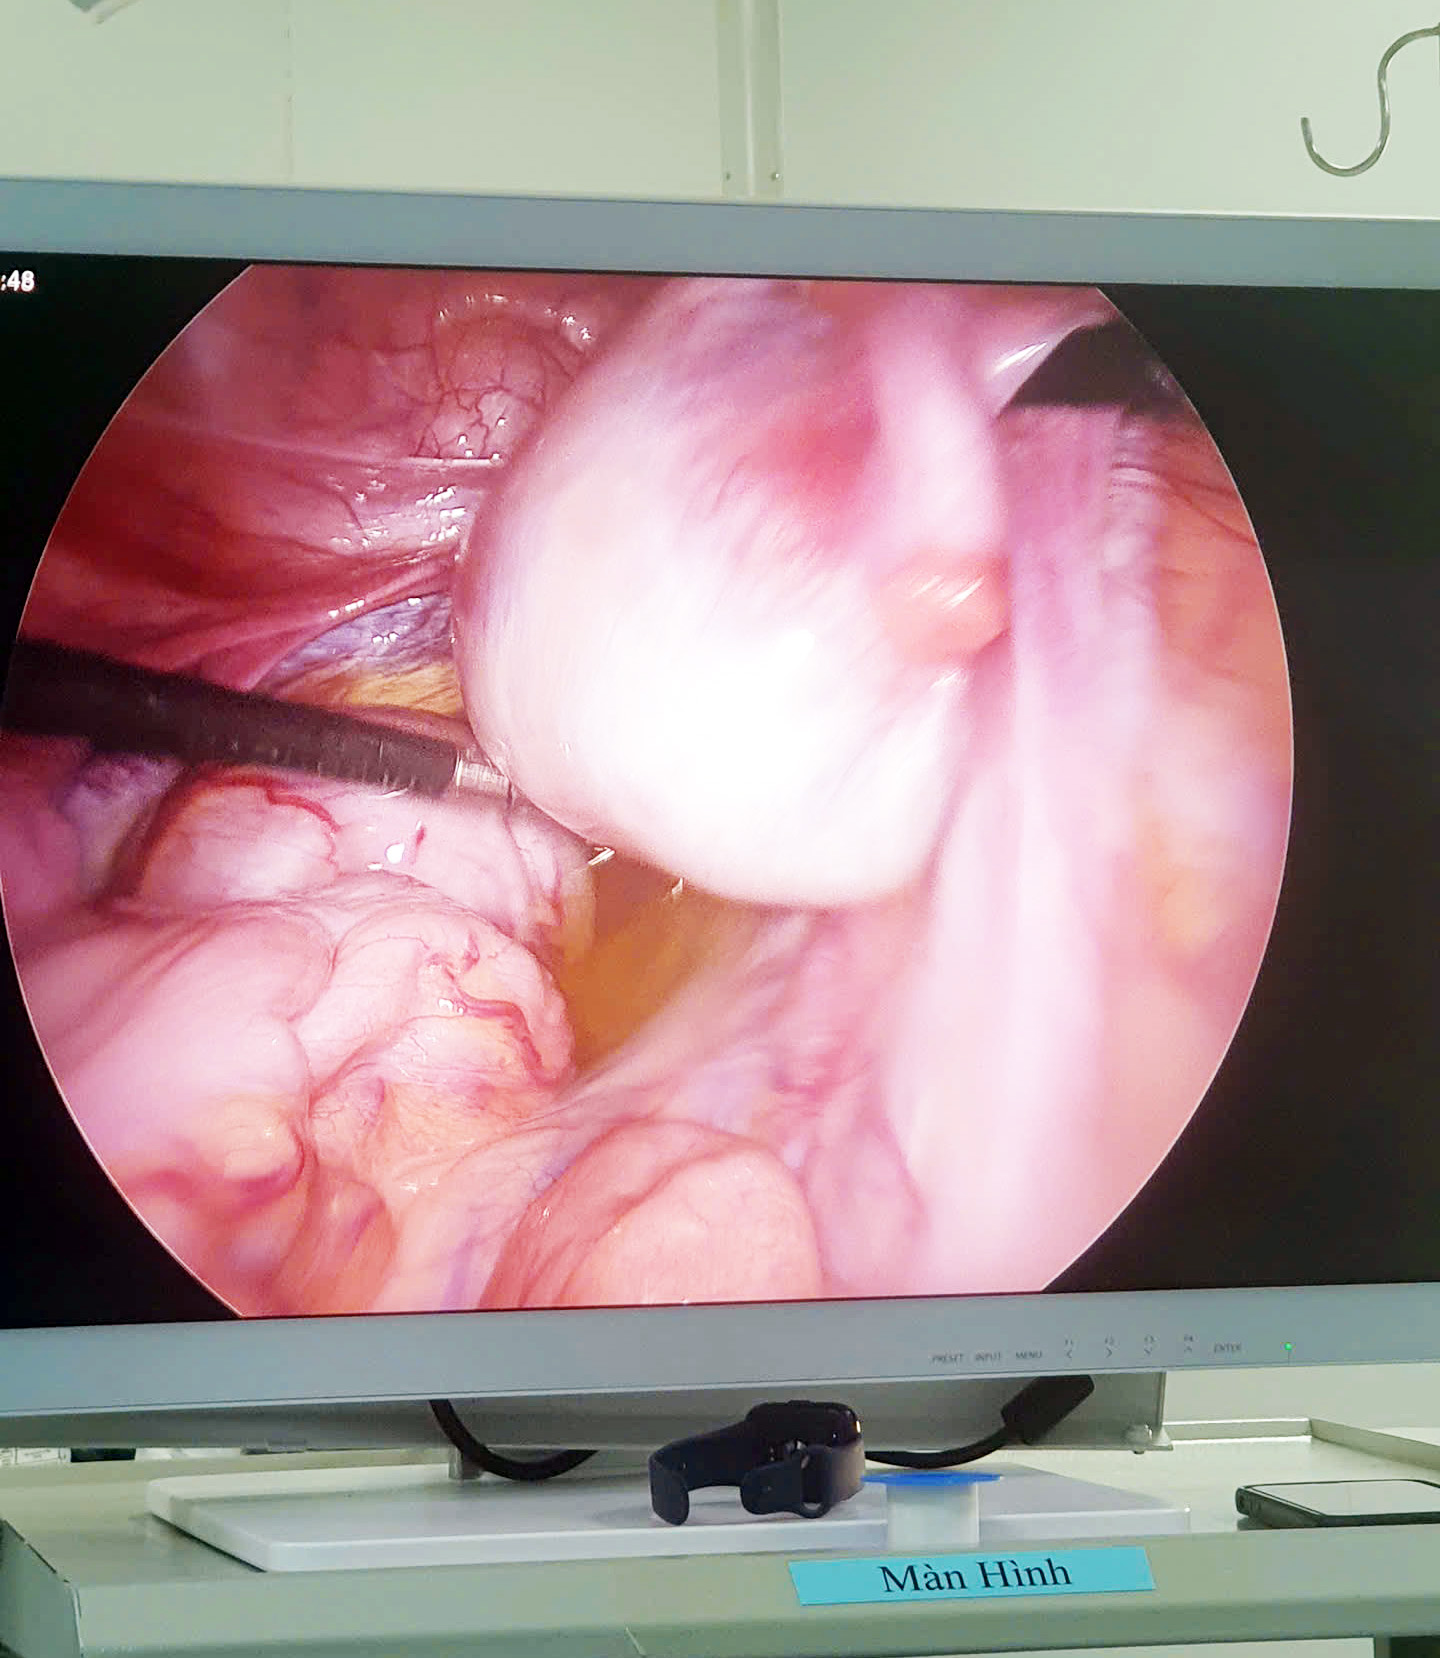

Các bác sĩ tiến hành đặt 03 trocart trên bụng và đưa camera vào thăm dò ổ bụng. Quan sát thấy phần vòi trứng trái và buồng trứng trái phát hiện và bóc tách loại bỏ khối u và bảo tồn phần buồng trứng lành cho trẻ. Bên trong khối u có tổ chức dạng mỡ, tóc, xương. Hiện tại sức khỏe bệnh nhân ổn định và sẽ được xuất viện trong vài ngày tới. Kíp mổ do các bác sĩ và các kỹ thuật viên giàu kinh nghiệm tại khoa Ngoại chuyên khoa và Gây mê hồi tỉnh phối hợp thực hiện.